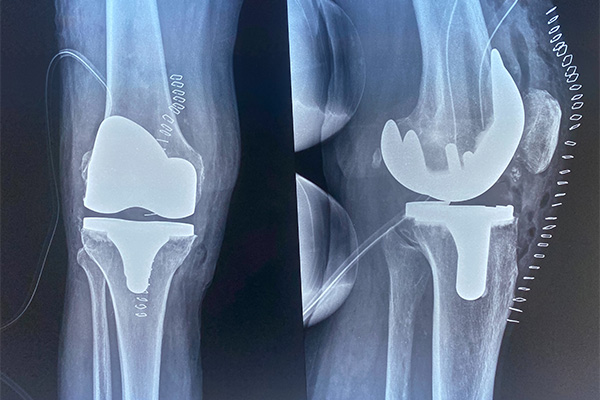

Η δύσκολη και λεπτή επέμβαση έγινε σε 76χρονο ασθενή και στην χειρουργική ομάδα του κ. Μαρκόπουλου συμμετείχαν οι: Ανδρέας Ιγνατίδης (ειδικός ορθοπεδικός), Μιχάλης Χαρίσης και Γεώργιος Κοπανιάρης (ειδικευόμενοι) καθώς και η Διευθύντρια του αναισθησιολογικού τμήματος κα Παναγιώτα Δώμου.

Η επέμβαση ήταν απόλυτα επιτυχής και αποτελεί την πρώτη επέμβαση επανορθωτικής χειρουργικής που πραγματοποιείται με σύστημα πλοήγησης - navigation και διενεργείται σε περιφερειακό νοσοκομείο.

Όπως τόνισε στο eidisis.gr ο κ. Μαρκόπουλος, «η συγκεκριμένη εξειδικευμένη επέμβαση συγκριτικά με την κλασική επανορθωτική επέμβαση γόνατος επιτρέπει την ακριβή εξισορρόπηση του εύρους κίνησης της άρθρωσης, λαμβάνοντας υπόψη τις εξατομικευμένες ιδιαιτερότητες του κάθε γόνατος. Οι οστεοτομίες της άρθρωσης είναι πλέον αποτέλεσμα της χαρτογράφησης των στοιχείων αυτής από ψηφιακά καθοδηγούμενη πλοήγηση και δύναται να είναι μετρήσιμες.

Η επανορθωτική χειρουργική του γόνατος με το σύστημα πλοήγησης - navigation αποτελεί σίγουρα την νεότερη εξέλιξη της επεμβάσεως και θα αποτελέσει ένα ακόμη σύγχρονο εργαλείο στην χειρουργική φαρέτρα της Ορθοπεδικής Κλινικής του Γ.Ν. Κιλκίς στην αντιμετώπιση της βαριάς οστεοαρθρίτιδος».